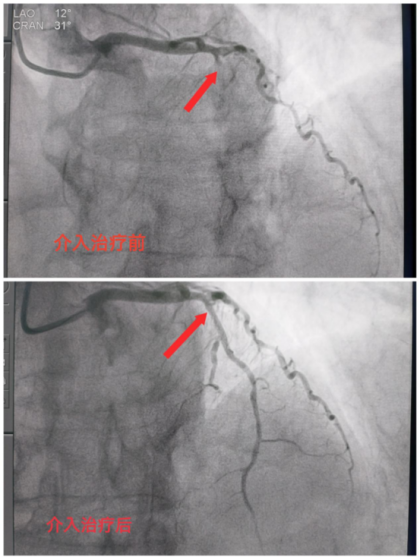

手术由心内科许波副主任医师主刀,术中冠状动脉造影发现冠状动脉前降支中段发出第一对角支后闭塞;回旋支近段最重狭窄70%;右冠状动脉近段最重狭窄30%,中段最重狭窄40%,远段最重狭窄30%,相当于整个心脏1/3血液供应缺失。冠状动脉的作用相当于汽车发动机的油路一样,发动机油路堵塞就会熄火,心脏也一样;而前降支又是冠状动脉中非常重要的一支血管,相当于我们房子的承重墙一样,所以患者的心脏处于崩溃的边缘。手术团队紧急输送导丝通过闭塞病变、球囊扩张并植入支架一枚,成功开通闭塞血管,恢复了远端血流,经手术团队及胸痛中心各部门紧张、平稳、有序地通力合作,从患者到达导管室到闭塞血管恢复血流用时仅21分钟,成功抢救了这位百岁老人的心肌与生命。同时刷新了阆中市人民医院老年人急诊介入治疗年龄高限记录。